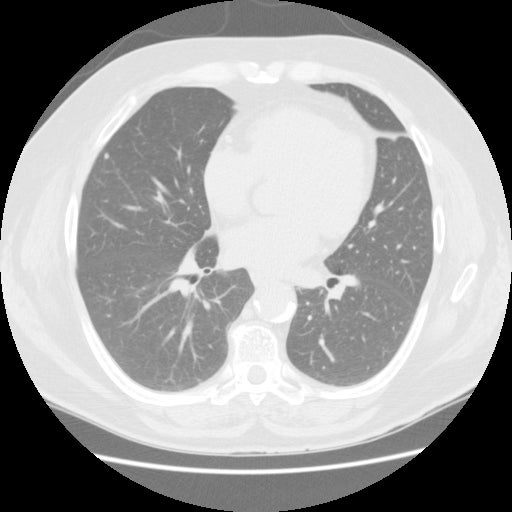

【EIRL Chest CTによる表示例】

② 低線量CT